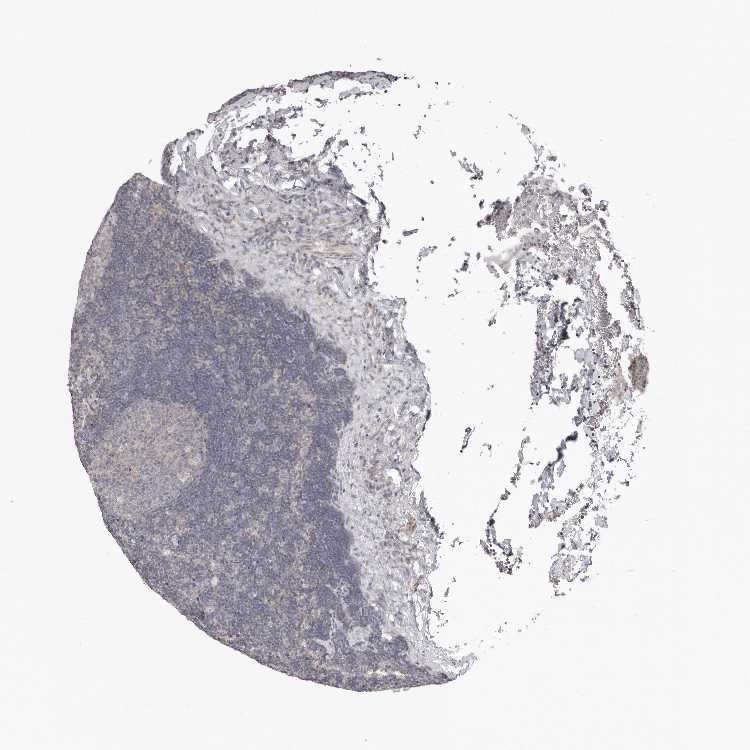

Information about each individual sample is listed below, including gender, age, a tissue section image and estimated fractions of cell types. nTPM (normalized transcripts per million) values give a quantification of the gene abundance which is comparable between different genes and samples.

Male, age 34

Lymph node sample 173

nTPM: 9.6

Cell types%

Lymphocytes:

85

Other cell types:

overview

Female, age 29

Lymph node sample 174

nTPM: 13

95

Female, age 61

Lymph node sample 175

nTPM: 9.8

Female, age 83

Lymph node sample 176

nTPM: 8.9

Female, age 52

Lymph node sample 177

nTPM: 10.5

5